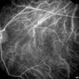

- Macular teleangiectasia

- macular telangiectasia

- Janusz Michalewski, MD, PhD, Ophthalmic Clinic "Jasne Blonia", Lodz, Poland

Optical coherence tomography system

Heidelberg Spectralis - Description

- Late phase fluorescein angiography of a 56-year-old woman.